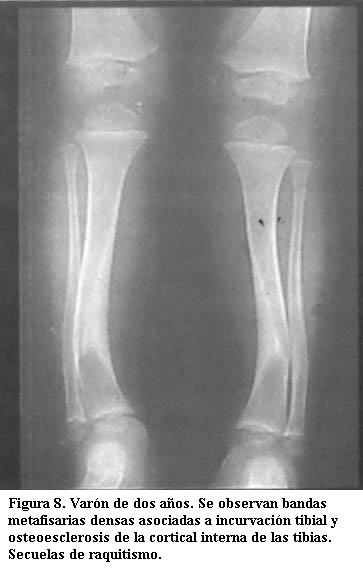

Raquitismo

En la etapa de reparación aparece una banda de calcificación metafisaria semejante a una banda de plomo. Pero además las metáfisis pueden estar ensanchadas, está engrosada la cortical interna de las tibias y puede haber incurvación tibial. Actualmente el raquitismo es raro (figura 8) (4).